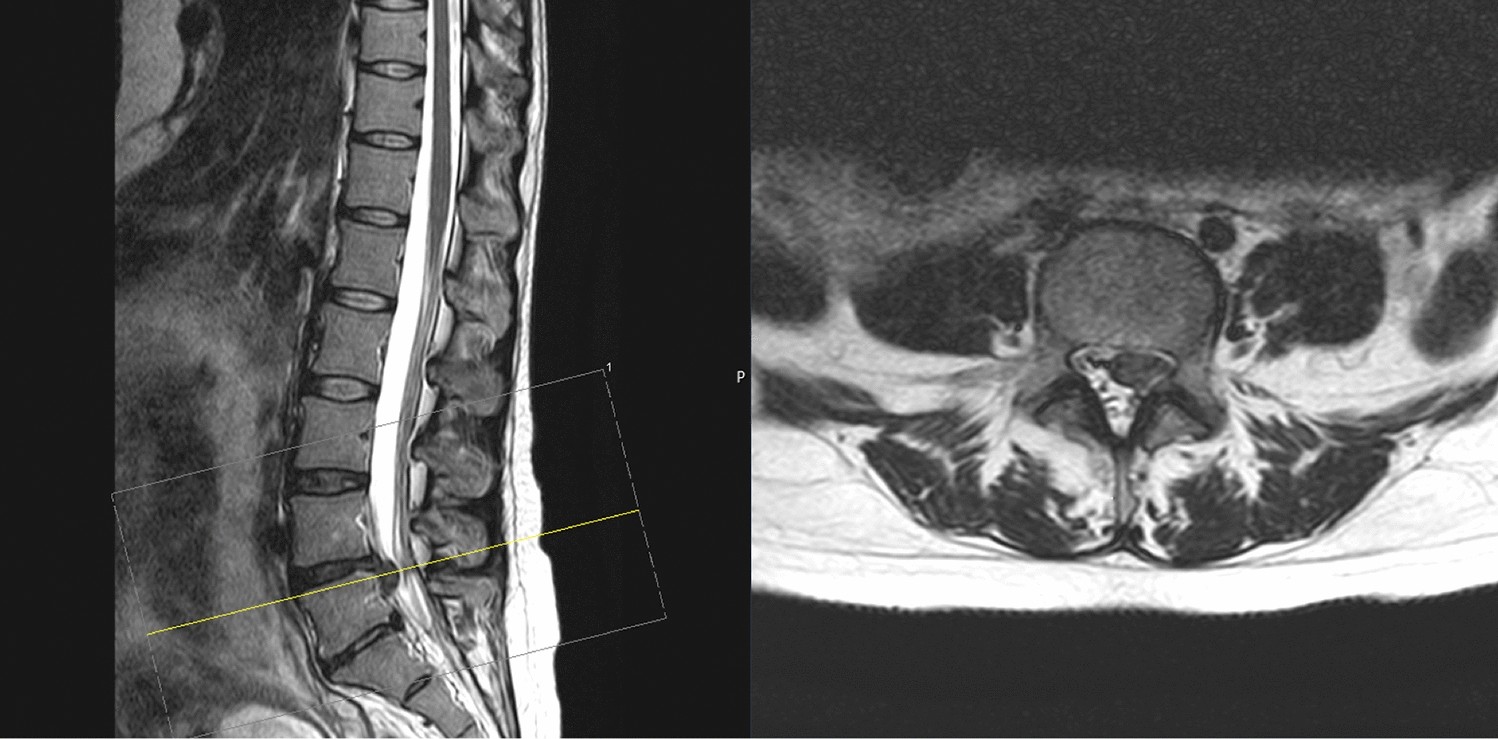

Fig. 3

MR imaging of the lumbar spine with sagittal (left) and axial (right) sequencing showing a disk prolapse at the level L4/L5 in a pregnant woman with left foot extension paresis